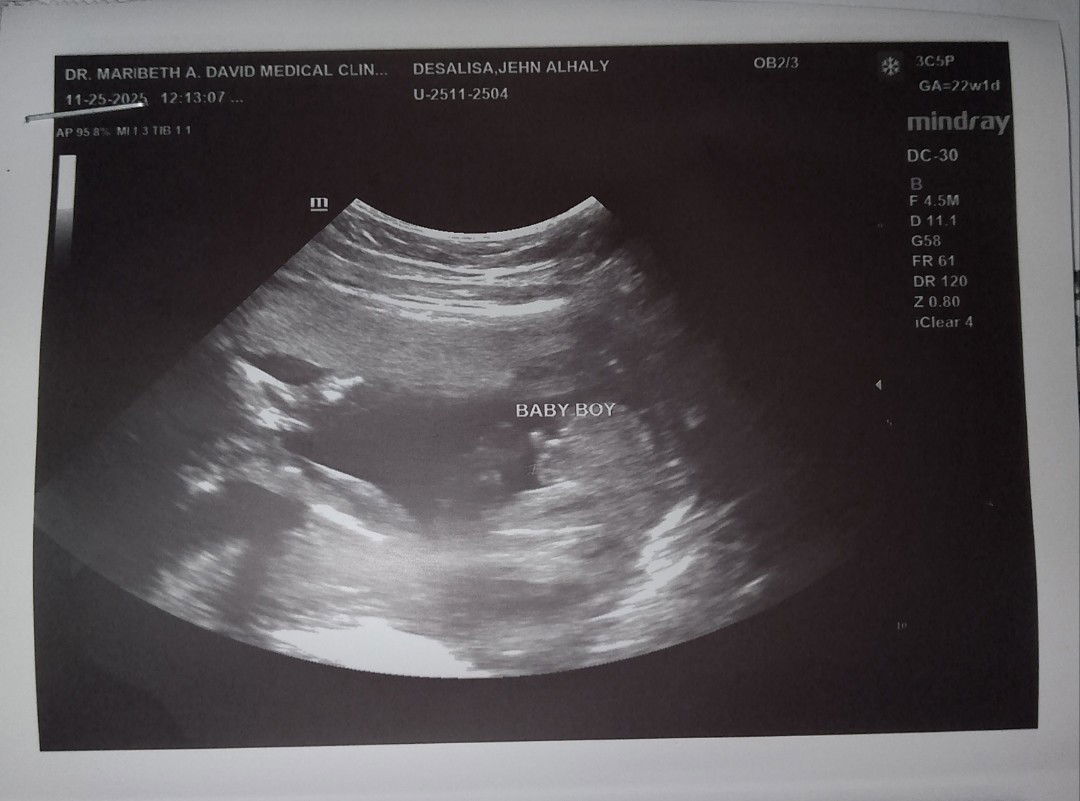

Normal lng po ba results ng lab urinalysis ko thanks po sa sasagot pst respect 🫵😊 #BabyBoy22weeks

may konting UTI po...drink more water po..no need to worry naman..kaya pa ng water therapy po..